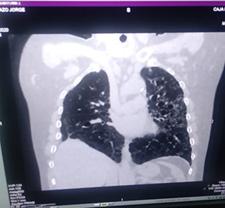

Paciente COVID-19 con trombosis e infarto agudo de miocardio

Reporte de Caso Clínico

COVID-19 patient with thrombosis and acute myocardial infarction

Rommer Alex Ortega Martínez

Gabriela Vaca Mendoza